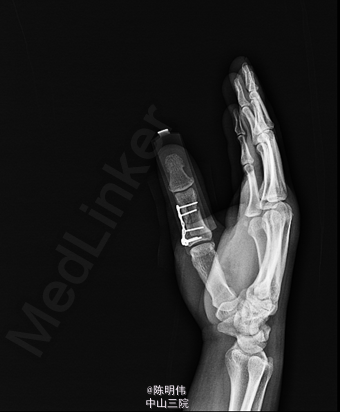

入院后完善相关检查,无明显手术禁忌,行右拇指近节指骨骨折切开复位内固定术,术程顺利,术后镇痛、改善循环治疗,并加强手术伤口换药。

患者挤压伤,能够尽早手术对患指的恢复非常重要。该患者行钢板固定术后影像不错,为何不考虑克氏钉固定呢

患者受伤机制明确,X线骨折移位明显,内固定术处理得很好,要注意术后康复恢复。